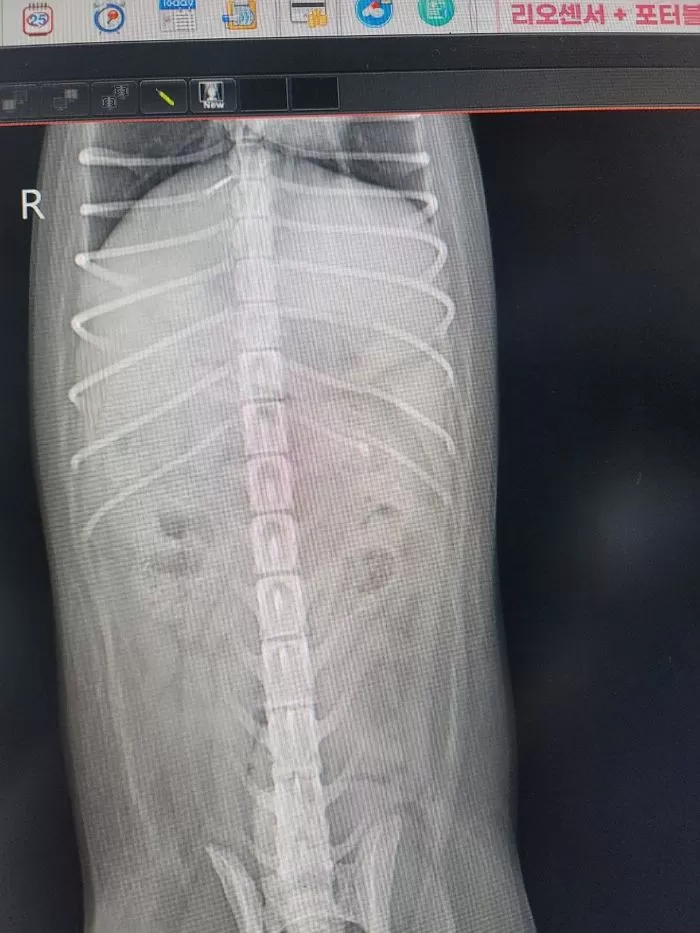

A씨는 놀란 마음에 집 근처 24시 동물 병원을 급히 찾아 이것저것 검사를 했더니 갈비늑골 3개가 부러져있고 두개골 파열에 복부 멍 자국, 신경계 이상 등 강아지의 몸 상태는 매우 처참했다.

검사 결과 두개골 골절로 인한 뇌출혈 및 우뇌 이상 소견을 받았다. 수의사는 "이런 외상은 단순 높은 곳에서 떨어져서 생길 수 있는 게 아닌 폭력이 상당히 의심된다"고 설명했다.